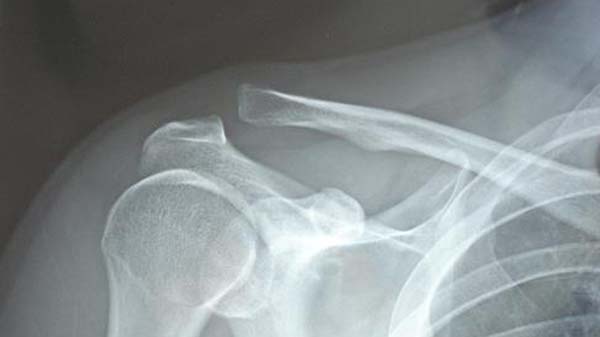

脱臼